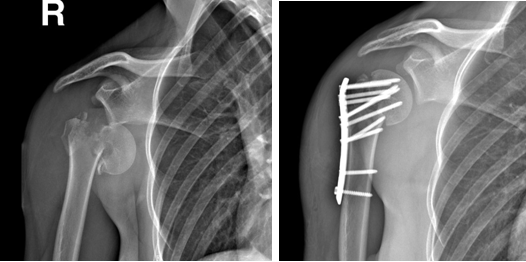

肩关节骨折

病例一:

女性22岁,车祸伤右肱骨近端骨折并肱骨头脱位,行切开复位钢板螺钉内固定手术。

术前                         术后

术后1年取内固定

术后